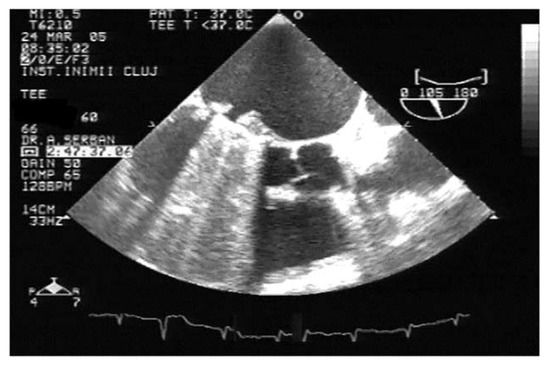

TEE is the gold-standard imaging method for MVT diagnosis, especially when mechanical prosthesis obstruction is caused by thrombosis [1,9,23,24,25,26]. Due to the proximity of the esophagus to the left atrium, the atrial face of any type of mitral prosthesis is accessible (Figure 4, Video S2, Supplementary Material). In the presence of obstructive thrombosis, the mobility of the discs is reduced or even blocked [23,24,27].

Figure 4.

TEE. Thrombus on the atrial side of mechanical mitral prosthesis (arrow).